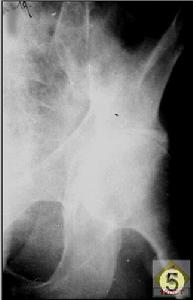

2、X線檢查

骨性關節炎早期X線檢查正常。稍後逐漸出現關節間隙狹窄,反映覆蓋在皮質上的關節軟骨層變薄。最後,骨性關節病進行性發展,關節間隙明顯變窄,關節緣變銳,於邊緣出現骨刺或骨贅(osteophyte)形成,軟骨下骨增厚和硬化,於軟骨下骨受壓最大部位發生骨囊腫。X線拍片陰性並不能排除骨性關節炎。相反,X線檢查有典型表現,也不能肯定是原發性骨性關節炎。退變性改變常常同時存在其他疾病,痛風、感染性關節炎和類風濕性關節炎值得注意。